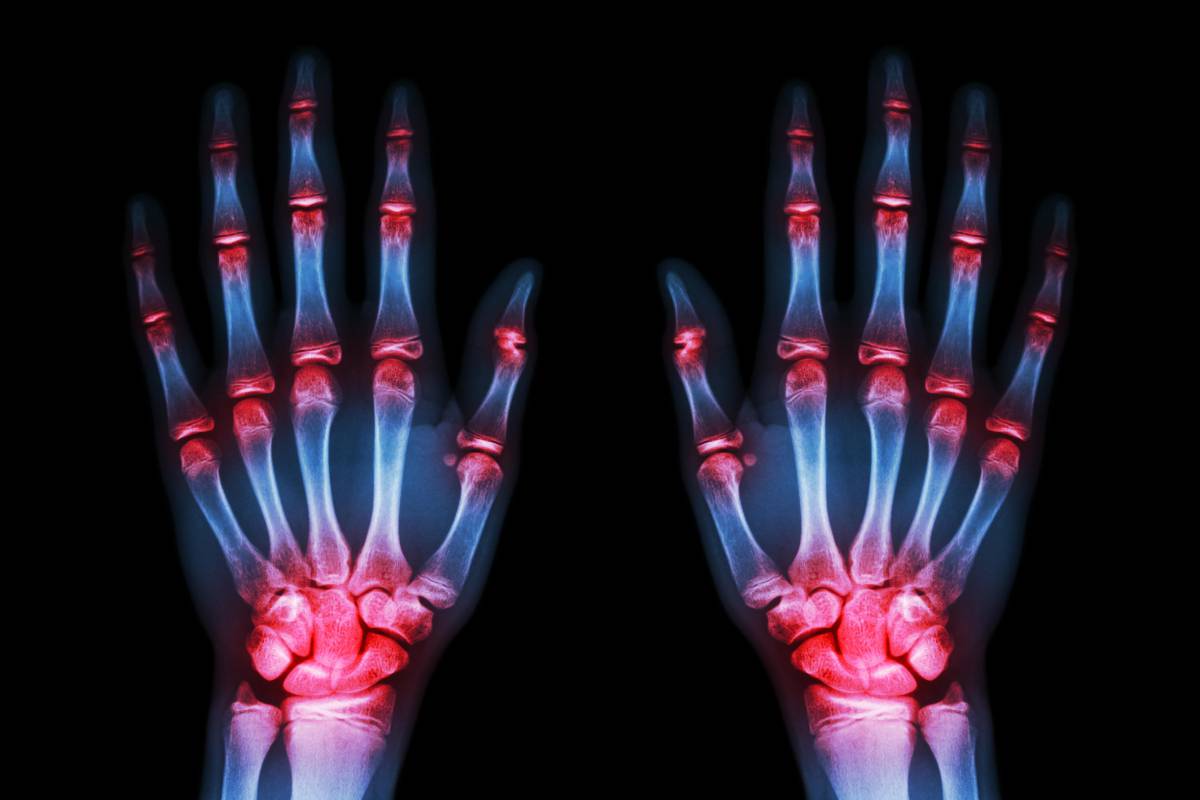

当血液中尿酸浓度过高,超过了尿酸的溶解度时,在关节和周围软组织就会析出尿酸盐结晶沉积,诱发炎症刺激,产生剧烈疼痛,进而出现反复发作的急性关节炎和软组织炎症。长期痛风会刺激机体形成慢性异物肉芽肿反应,即痛风石,造成局部骨质缺损、关节畸形。别嘌醇可以降低血中尿酸水平,防止尿酸形成结晶沉积,预防痛风石形成,并可以使已经形成的尿酸结晶溶解。